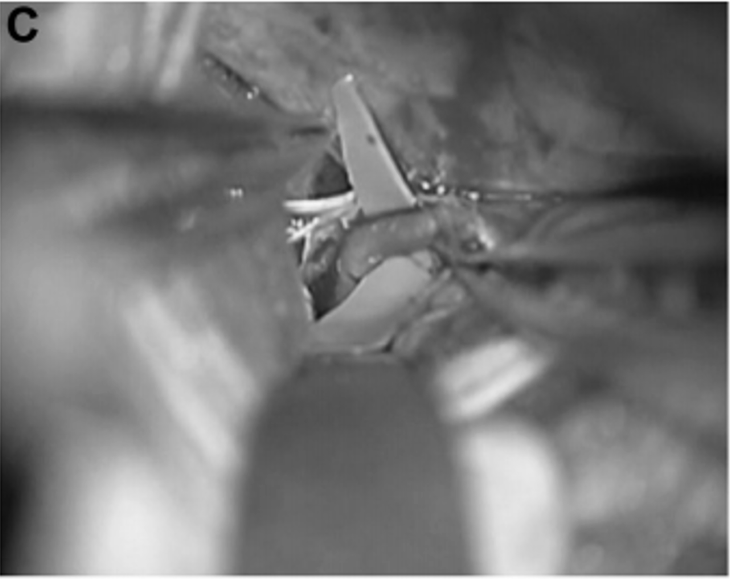

▼20天,经左颞下入路进行动脉瘤鼓励术和STA-PCA搭桥重建手术。初期夹闭动脉瘤的近端部分,同时保留丘脑穿支动脉。动脉瘤的解剖区域延伸到P2段后部,就在PTA分支点之前。在本例中,选择PTA作为受体动脉,因为其口径和角度优于P3段进行吻合(图3C和3D)。

C、D,受体动脉的PTA(箭头)。通过左颞下入路缝合STA和PTA之间的吻合。

进行STA-PTA旁路手术后,Kawashima教授将远端夹子放置在夹层动脉瘤上,同时保留穿支。术后1周血管造影显示,通过旁路到达左侧PCA区域的血流良好,并且动脉瘤完全被排除(图3E)。两周后,患者出院回家,没有出现神经功能缺损。在1年随访中,患者改良Rankin评分为0,搭桥术仍然合适。

▼E:术后1周的颈外动脉血管造影显示整个左PCA的旁路血液供应良好(箭头)